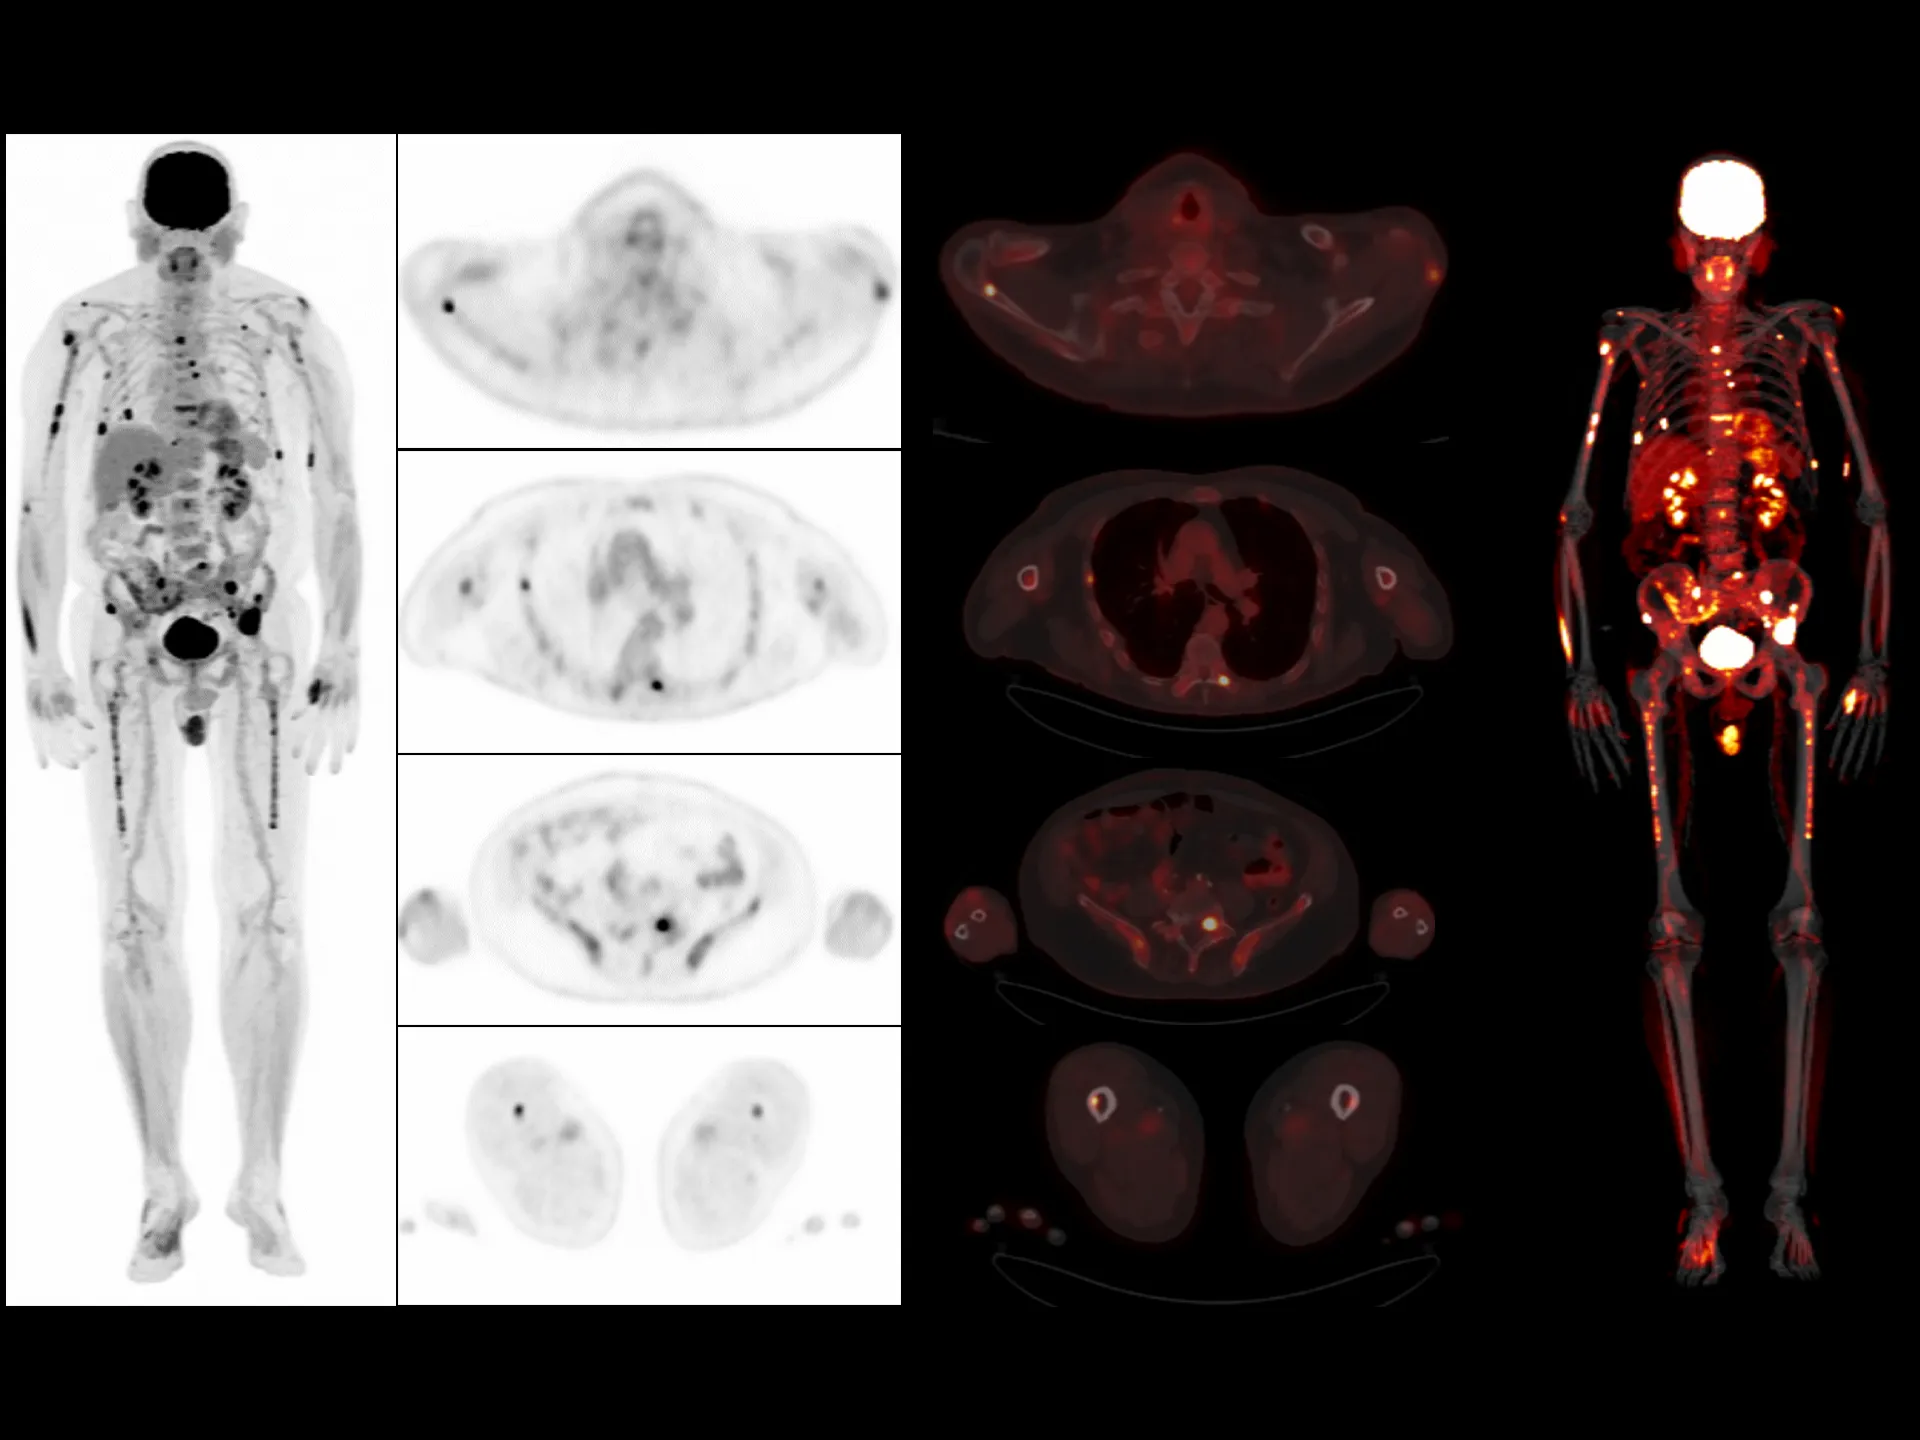

uMI Panvivo is a high performance PET/CT platform that moves state-of-the-art innovative advancement to clinical reality. It advances diagnostic precision with industry-leading NEMA spatial resolution of 2.9mm and time of fight (TOF) timing resolution of 219 picosecond (ps), while it’s air-cooled compact design make it more accessible to all. The human-centric design and fully AI-empowered workflow of uMI Panvivo deliver care to every patient while keeping the user in mind. Built on its scalable platform, uMI Panvivo’s powerful design builds the bridge toward long-term and sustainable success.

Driven by precision medicine and personalized care, uMI Panvivo offers the top-tier performance based on state-of-the-art detector technology and highly integrated system for better diagnostic confidence and capabilities.

Top-tier Performance

Leading TOF resolution that boosts small lesion detectability and clarity.

High effective sensitivity that benefits from TOF gain leverages better diagnostic accuracy under low dose usage and fast scan time.